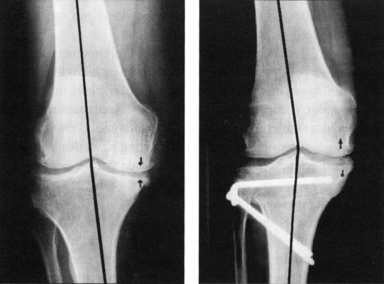

Left: Before the operation, an O-leg with a narrowing of the inside joint space (arrows).

Right: Through the osteotomy an intentional slight X-leg.

Bone assembly (osteosynthesis) having a plate and two screws.

The inner joint space is much larger (arrows).

The sick (inner) area is relieved.

The healthy (outer) area is loaded.